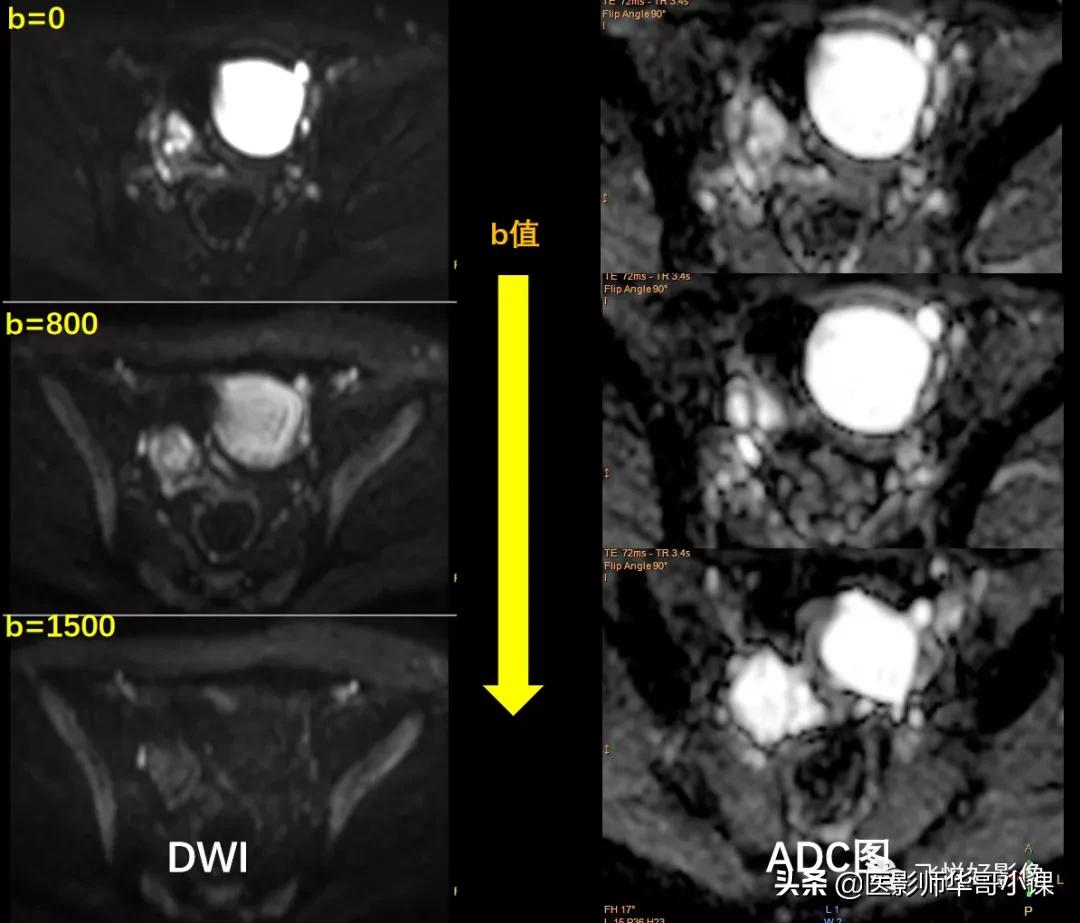

图3.DWI&ADC

双侧附件区囊性病变DWI(图3)图示随着b值的增加,病变信号明显减低,ADC图病灶未见明显低信号,考虑囊性良性病变。